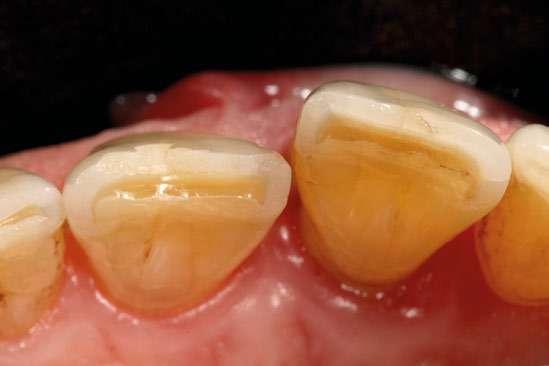

Presentamos el caso de un paciente masculino de 61 años de edad, bruxista, con evidentes desgastes en toda la dentición y cracks de esmalte que pueden observarse en las fotografías iniciales de la primera visita (figuras 1 y 2). En las fotografías

Figuras 1 y 2. Imágenes intraorales de la primera visita donde se hacen evidentes diferentes desgastes en los dientes anteriores y a mayor detalle crakcs en el esmalte, así como lesiones por abfracción en los cuellos de los dientes de los premolares y caninos superiores.

laterales se ponen de manifiesto aún más varias lesiones de esmalte que indican la parafunción en el paciente, unido a los desgastes excesivos en varias zonas (figuras 3 y 4). El paciente acude por dolor y movilidad en la pieza 11, que se ha incrementado en los últimos días, además de sensación de “diente crecido” que como podemos ver en las fotografías iniciales es real, ya que el diente se encuentra ligeramente extruido en relación con el contralateral. Estos signos parecen indicarnos una fractura o fisura. En la fotografía oclusal, podemos observar el desplazamiento del diente debido a la movilidad (figura 5). Posteriormente se realiza un sondaje positivo de la pieza, que lleva a 11 mm por lo que se confirma la sospecha de fractura y se procede a la exodoncia del diente, realizándose una regeneración posterior del alveolo con PRGF-Endoret y

Figuras 3 y 4. Fotografías laterales donde se evidencian los cracks de esmalte en varios dientes y los desgastes excesivos en varios puntos. En estas imágenes se hacen más evidentes las lesiones por abfracción.